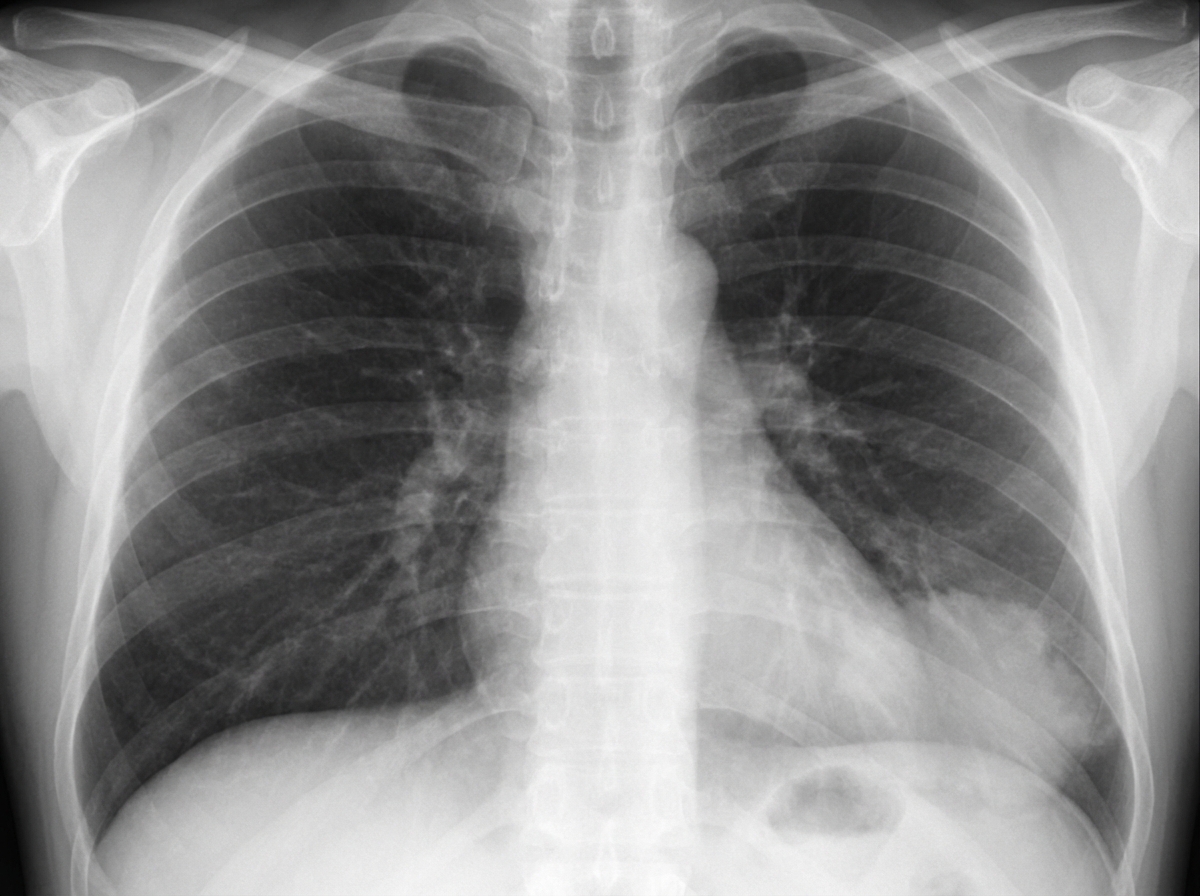

A 29-year-old woman presents with a history of recurrent respiratory tract infections. She has no significant travel history and denies any history of foreign body aspiration. On examination, coarse crackles are noted in the left lower lung zone. A chest X-ray reveals findings suggestive of a possible abnormality. Based on the history and chest X-ray findings, what is the most appropriate next diagnostic step?

Explanation: ***Contrast CT scan of the chest and upper abdomen*** • The combination of **recurrent respiratory infections** in a young patient with **left lower lobe involvement** strongly suggests **pulmonary sequestration**, which requires imaging the **upper abdomen** to detect aberrant **systemic arterial supply** from the **descending/abdominal aorta**. • **Contrast CT** is the gold standard for identifying the **anomalous vascular supply** and defining the anatomy of the sequestered lung tissue, which is essential for surgical planning. *Bronchogram* • This technique is **obsolete** and has been largely replaced by **high-resolution CT** and other advanced imaging modalities. • It involves injecting **contrast material** directly into the bronchial tree, which is **invasive** and provides limited information compared to modern CT imaging. *Bronchoscopy* • While useful for evaluating **airway anatomy** and obtaining tissue samples, it would not identify the **vascular abnormalities** characteristic of pulmonary sequestration. • It is typically performed **after imaging** has established the diagnosis and before surgical intervention, not as the initial diagnostic step. *Determination of serum immunoglobulin levels* • This would be appropriate if suspecting **immunodeficiency** as the cause of recurrent infections, but the **localized left lower lobe** involvement suggests a **structural abnormality** rather than systemic immune dysfunction. • **Immunoglobulin levels** would not explain the specific **radiographic findings** or help identify the underlying anatomical defect.